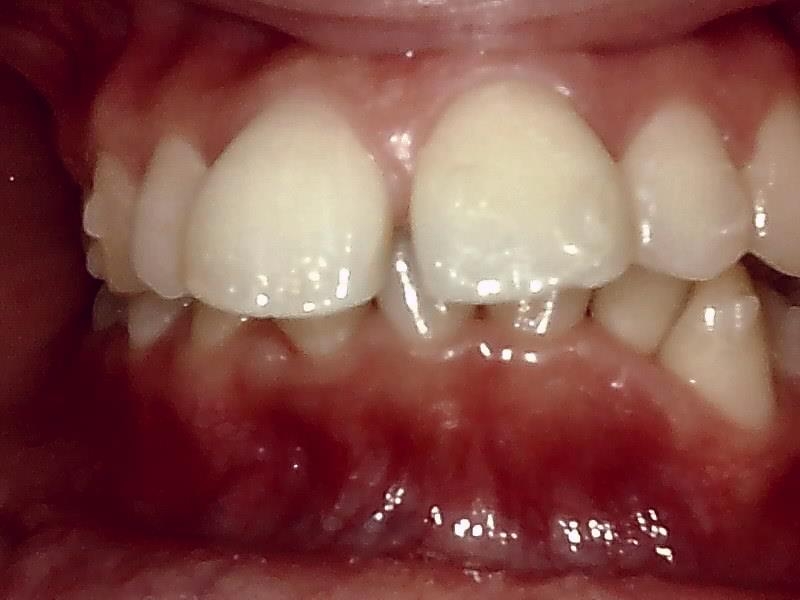

術前口腔内写真 正面観

○前歯の前突した歯を治したい

○笑った時の歯のアーチを綺麗にしたい